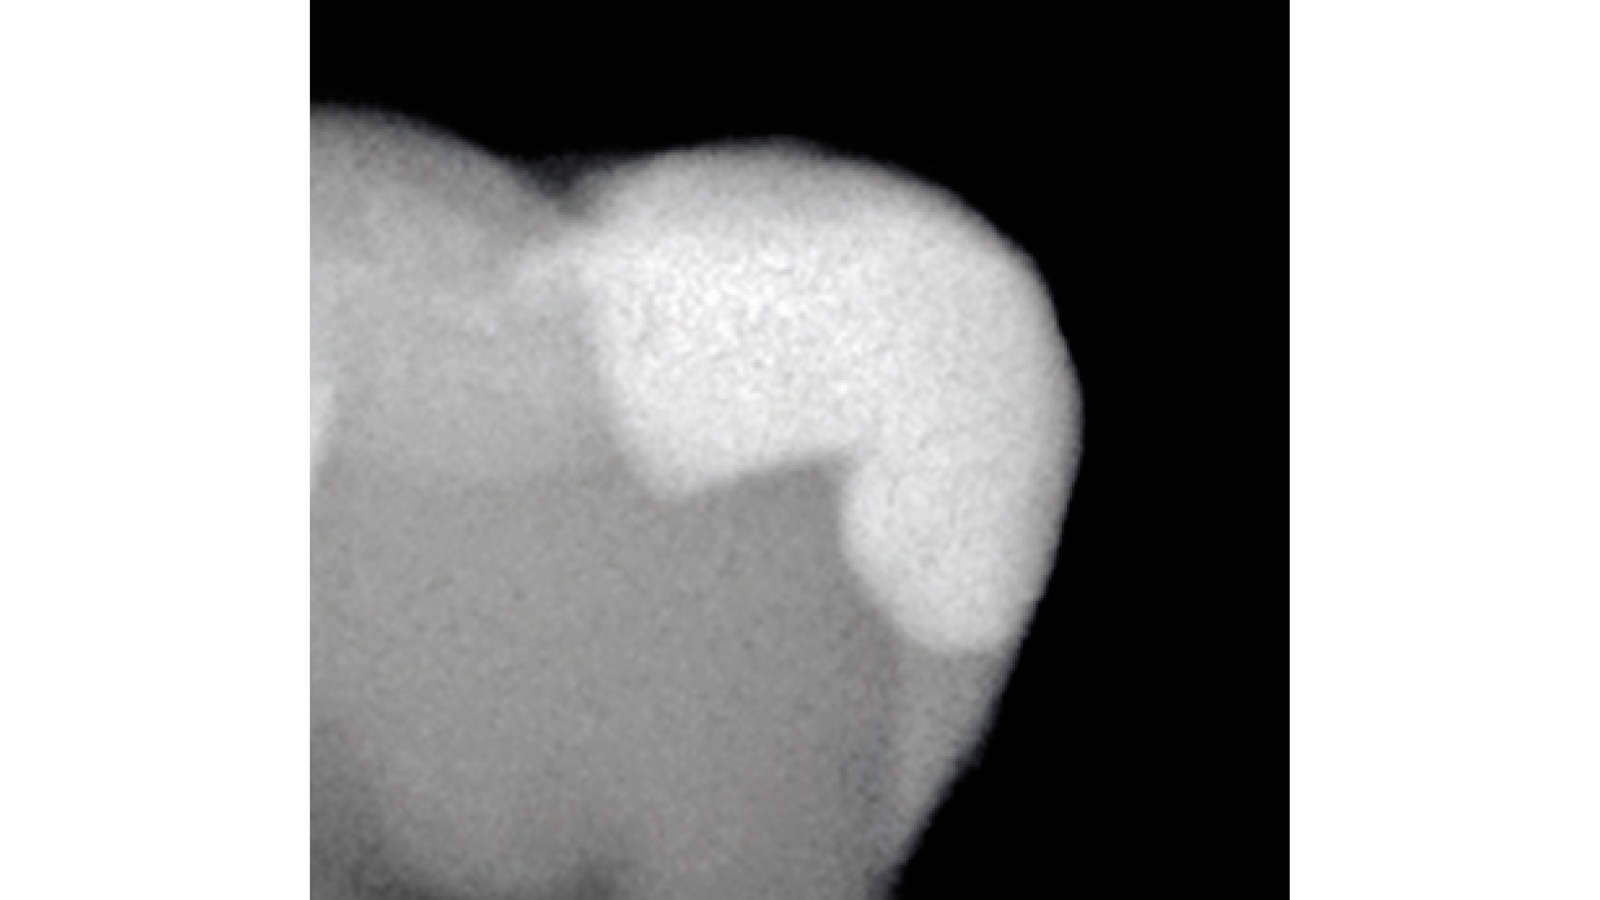

5) Is Venus Diamond Flow radio-opaque?

Yes, Venus Diamond Flow fillings are easily recognized on X-rays.